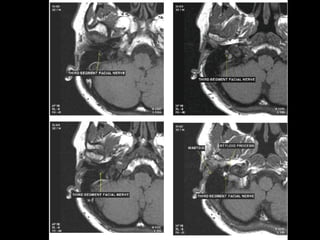

Facial nerve

 The facial nerve is one of the key cranial nerves with a complex and broad range of

functions.

 Although at first glance it is the motor nerve of facial expression which begins as a trunk

and emerges from the parotid gland as five branches it has taste and parasympathetic

fibres that relay in a complex manner.

 The facial nerve is the only cranial nerve that may show normal post-contrast

enhancement, although this applies only to the labyrinthine segment up to

the stylomastoid foramen. Enhancement of the other segments of the facial nerve and

other cranial nerves is considered pathologic.

Segments

 intracranial (cisternal) segment - zero branches

 meatal (canalicular) segment (internal auditory canal): 8 mm long, zero branches

 labyrinthine segment (IAC to geniculate ganglion): 3-4 mm long, 3 branches

(from geniculate ganglion)

 tympanic segment (from geniculate ganglion to pyramidal eminence): 8-11 mm

long, zero branches

 mastoid segment (from pyramidal eminence to stylomastoid foramen): 8-14 mm long, 3

branches

 extratemporal segment (from stylomastoid foramen to division into major branches): 15-

20 mm, 9 branches